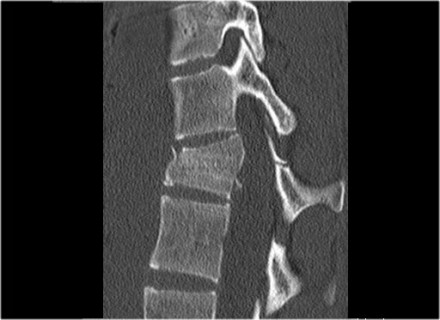

The images are of a patient with a typical bamboo spine as a result of ankylosing spondylitis.

After a fall on his back no fracture was seen on the x-rays.

However the CT shows a thin fracture line through the anterior side of the vertebral body and also through the spinous process.

Continue with the MR-images.